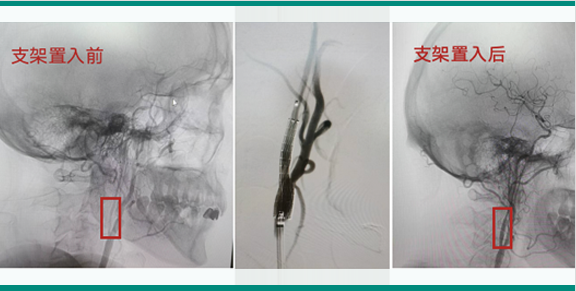

腦血管病診療中心聚集了一批擁有豐富臨床經(jīng)驗(yàn)和深厚學(xué)術(shù)背景的腦血管病專家。中心專注于腦血管疾病的預(yù)防、診斷、治療及康復(fù),主要診治各類腦血管疾病,如顱內(nèi)動(dòng)脈瘤、蛛網(wǎng)膜下腔出血、腦血管畸形、煙霧病、硬腦膜動(dòng)靜脈瘺、顱內(nèi)靜脈系統(tǒng)疾?。ㄈ珈o脈竇血栓、靜脈梗塞引起的腦梗死或腦出血)、外傷或自發(fā)性海綿竇內(nèi)動(dòng)靜脈瘺(CCF)、脊髓內(nèi)血管畸形、髓周動(dòng)靜脈瘺、硬脊膜動(dòng)靜脈瘺、腦和脊髓的海綿狀血管瘤,顱內(nèi)血管狹窄、頸動(dòng)脈狹窄、椎-基底動(dòng)脈狹窄、鎖骨下動(dòng)脈狹窄、顱內(nèi)和頸部的血管夾層、顱內(nèi)或頸部血供豐富的腫瘤術(shù)前栓塞或化療等。從疾病的早期篩查、診斷到治療及后期康復(fù),我們提供全面的診療服務(wù)。

精通顱內(nèi)動(dòng)脈瘤介入栓塞和手術(shù)夾閉雙技術(shù),系統(tǒng)掌握腦動(dòng)靜脈畸形、頸內(nèi)動(dòng)脈海綿竇漏、硬腦膜動(dòng)靜脈漏等顱內(nèi)血管疾病的診療和手術(shù),精通頸動(dòng)脈、椎動(dòng)脈狹窄的血管內(nèi)重建技術(shù),以及頸動(dòng)脈狹窄的內(nèi)膜剝脫手術(shù)技術(shù)。在顱內(nèi)腫瘤、椎管內(nèi)腫瘤、顱腦損傷、高血壓腦出血等疾病的診治和手術(shù),腦功能性疾病立體定向手術(shù)治療等方面也積累了豐富的經(jīng)驗(yàn)。

擅長(zhǎng)腦血管病(出血與缺血)的神經(jīng)介入與微創(chuàng)手術(shù),能熟練開(kāi)展腦外傷、重度顱腦損傷的救治工作。